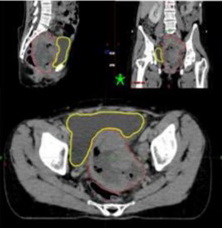

Fig. 1. Ct image simulation of sagittal, cortical and axial pieces with residive mass on the vaginal punctum (red). Note that “Fig.” is abbreviated. There is a period after the figure number, followed by two spaces. It is good practice to explain the significance of the figure in the caption.